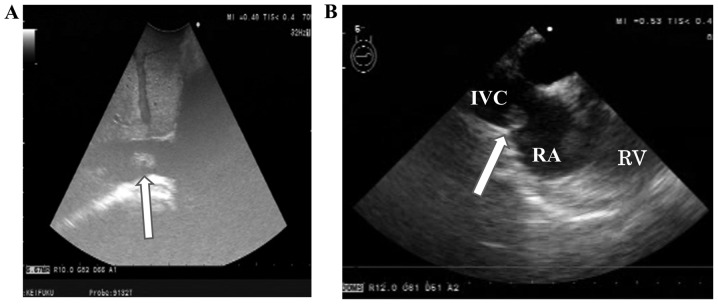

Subsequently, the vascular surgery team took over to remove the intravascular tumor. On preoperative planning, the tumor was present below the level of the renal veins; however, a perioperative ultrasound scanning of the IVC revealed a free-floating tumor in the form of a thin multinodular plate extending to the right atrium (Fig. 3). Manipulation of the liver was required, but was associated with the risk of tumor pulmonary embolisation. a cardiovascular surgery team performed emergency thoracotomy with median sternotomy and removed the intracardiac tumor through cardiotomy of the right atrium using extracorporeal circulation without circulatory arrest. After closing the heart, a radiologist inserted a filter in the IVC immediately below the right atrium and the vascular surgery team exposed the IVC behind the liver, cut the vessel wall open and removed the intravascular tumor under IVC cross-clumping (Fig. 4).

Figure 3.

Perioperative ultrasound scan of the inferior vena cava. (A) Transabdominal echogram showing a free-floating tumor in the IVC behind the liver. (B) Transesophageal echogram showing the tip of the intravascular tumor in the right atrium. IVC, inferior vena cava; RA, right atrium; RV, right ventricle.